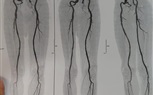

في إنجاز طبي جديد يُضاف إلى سلسلة النجاحات التي تحققها جامعة كفر الشيخ في المجال الطبي، نجح فريق جراحة الأوعية الدموية بمستشفى كفر الشيخ الجامعي في إجراء عملية جراحية متقدمة لإصلاح تمدد ضخم بالشريان الأورطي البطني والشرايين الحرقفية بالحوض باستخدام شريان صناعي متفرع، وذلك لأول مرة داخل محافظة كفر الشيخ.

والجدير بالذكر، أن العملية التي أُجريت بنجاح هي من العمليات الدقيقة والمعقدة جدًا، والمعروفة طبيًا باسم

Aorto bi-iliac bypass with re-anastmosis of IIA using a pantaloon graft for a huge AORTOILIAC aneurysm، وقد خرجت الحالة بحمد الله بسلام وصحة تامة بعد أن تم التعامل مع التمدد الضخم بدقة وكفاءة عالية.